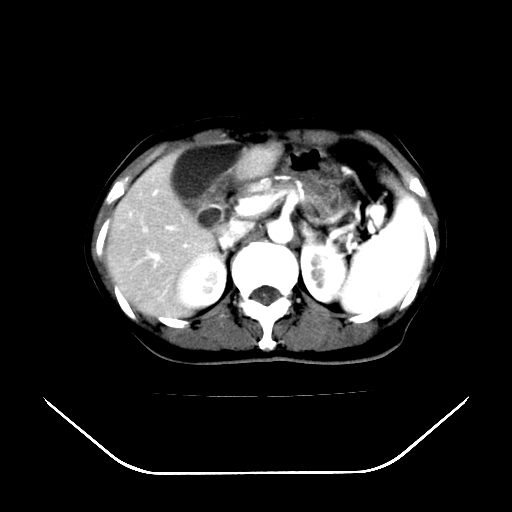

男,71岁,皮肤黄染四天。

肝内外胆管及胆总管上段扩张,考虑为梗阻所致,建议mrcp检查。

考虑胆总管癌并肝内外胆管扩张。

胰腺上端胆总管内见软组织影,强化不明显,结合临床,还是考虑低位梗阻性黄疸,胆总管癌可能性大